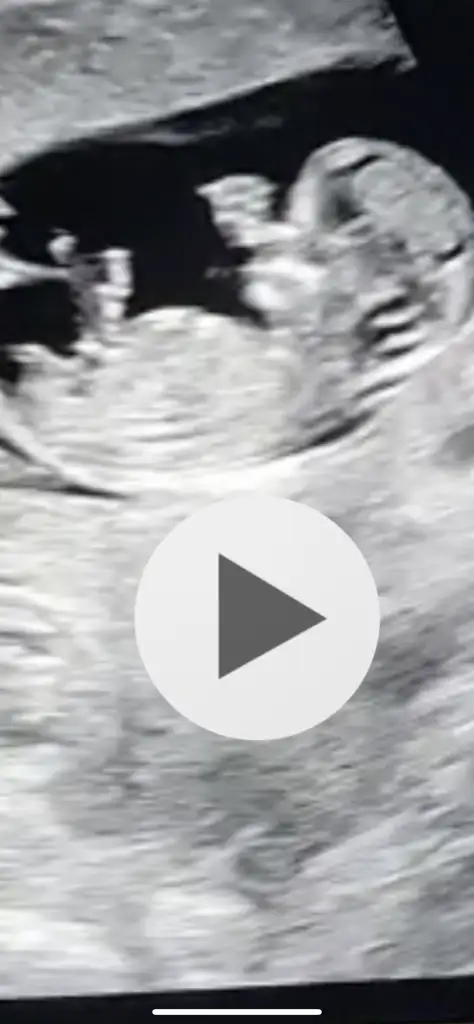

Ikra meyra tahmin rica edebilirmiyim 12 haftalık olduk .10 haftalık iken atmıştım ama arada kaynadı sanırım